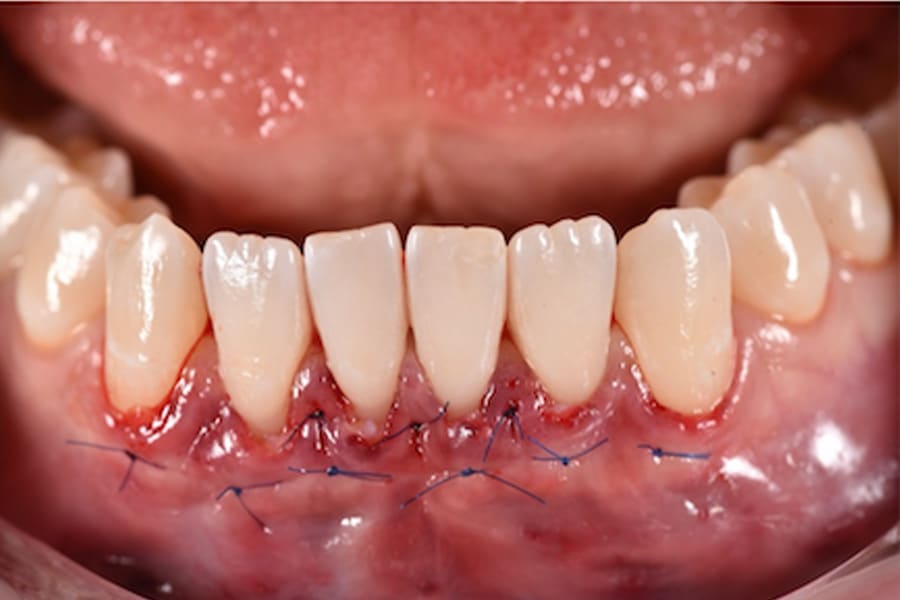

Periodontal Management and Thin Phenotypes

In thin phenotypes with early recessions, minimally invasive tunneling with CTG (with enamel matrix proteins on exposed roots when indicated) can increase soft-tissue thickness and support long-term stability after orthodontic tooth movement.12-16 (Figure 14 through Figure 17)